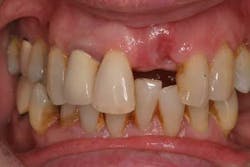

One prevalent shortcut that a practitioner can take is the failure to diagnose/treat periodontal disease prior to implant therapy. Because treatment of gingivitis and periodontitis can delay the placement of an implant fixture, both the practitioner and the patient may be tempted to avoid or postpone therapy until implant treatment is completed (Fig. 1).

This financially expedient decision can have untoward consequences in terms of implant success. Numerous studies have shown that the composition of the microflora for both periodontitis and peri-implantitis is the same (4). In addition, other studies suggest that bacteria from a periodontally involved tooth can subgingivally colonize an implant placed in the same mouth within a two-week period of time (5). Overwhelming evidence suggests that periodontal therapy needs to be initiated prior to implant therapy in order to decrease the bacterial load that can infect dental implants and cause peri-implantitis. Other studies have shown that even in edentulous patients, periodontal pathogens can be located in reservoirs such as mucous membranes, saliva, and the pharynx. These bacteria can reinfect new dental implants placed in these patients, especially if they do not follow a proper hygiene and maintenance schedule (6). Because of these compounding variables, many studies suggest that there is an increase in biological complications associated with implants placed in patients who have untreated periodontal disease. In addition, patients with treated periodontal disease who received dental implants had a higher incidence of peri-implantitis when they were not on placed on a strict maintenance schedule when compared to those patients who were (7). For example, although the dental implant may not fail, the periodontally involved teeth next to an implant can develop problems and act as a conduit of bacteria to the adjacent implant (Figs. 2a and 2b). These bacteria can contaminate the dental implant and cause it to fail. In addition, common sense would also tell us that many of our patients have lost their teeth due to neglect and/or improper home care. Implants, although resistant to caries, are not immune to peri-implantitis or failure due to the same neglectful habits.